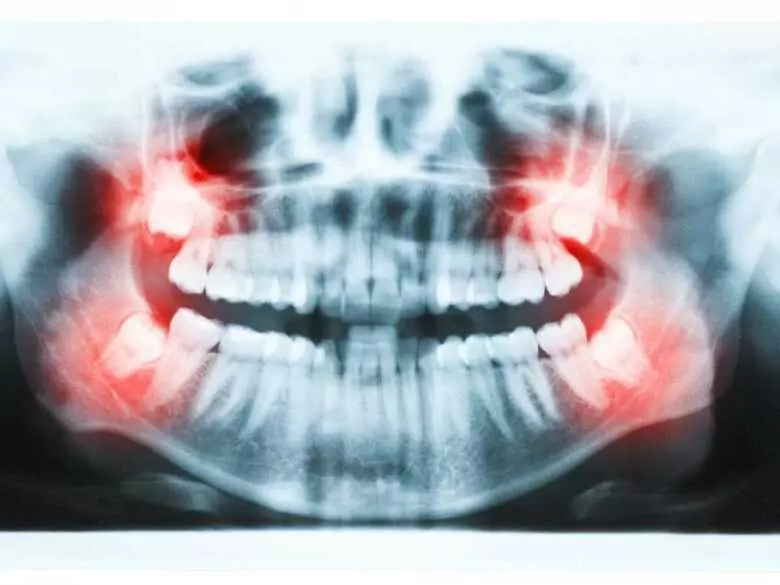

Radiografía de los dientes